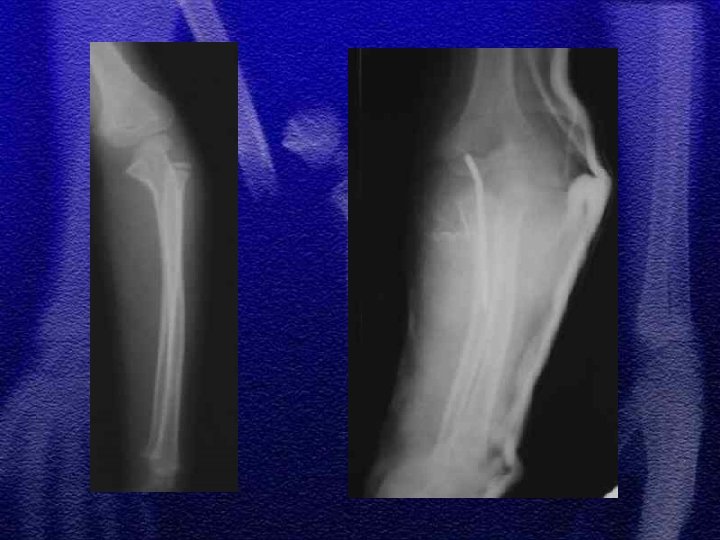

§ Najczęściej występuje typ wyprostny 85% § Wśród złamań typu Monteggia notuje się największą ilość błędów diagnostycznych § Leczenie - próba nastawienia zachowawczego, leczenie operacyjne przy niepowodzeniu repozycji zachowawczej § Należy pamiętać o możliwości wtórnego przemieszczenia odłamów

§ Podział

§ Specyficzne - to złamanie typu „zielonej gałązki”, przy złamaniach tego typu okostna nie jest uszkodzona całkowicie, dotyczy to również warstwy korowej § Przy repozycji należy złamać pozostałą warstwę korową, ponieważ zapobiega to wtórnemu przemieszczeniu

§ U dzieci starszych podobnie jak u dorosłych przydatny jest podział dotyczący lokalizacji złamania - określający 3 strefy złamania § W wieku rozwojowym rzadko występuje złamanie typu Galeazzi odmiana dziecięca to złamanie dalszej przynasady kości promieniowej ze złuszczeniem dalszej nasady kości łokciowej